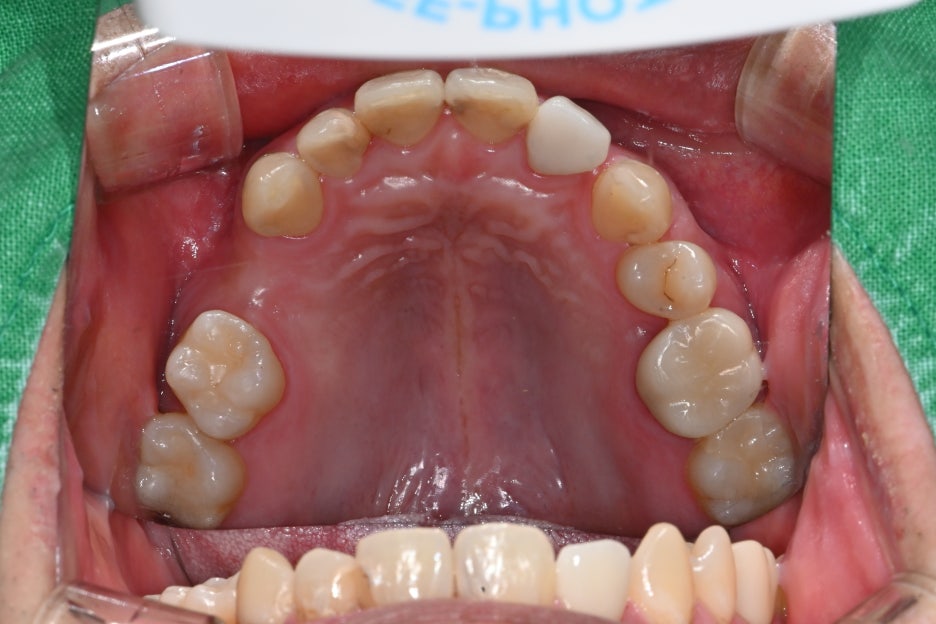

Photo at the first visit

Since the lower right molar broke, chewing causes pain

and discomfort.

In addition, because the upper right molar is missing,

food does not chew well.